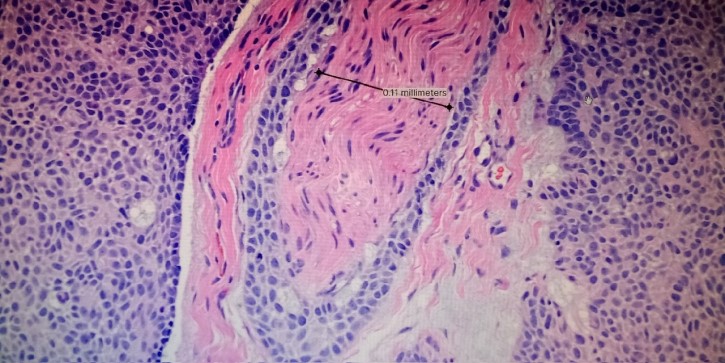

Dermatologists study pathology to diagnose and treat tumors. In this image, an aggressive basal cell carcinoma invades a nerve.